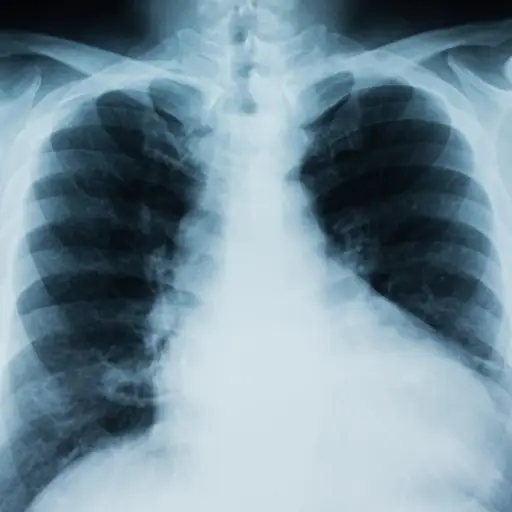

7种方式你所爱的人可以降低肺癌风险

因为你的直接如果您患有这种疾病,家庭成员可能会增加肺癌的风险增加,这里有一些提示对他们有利的赔率。